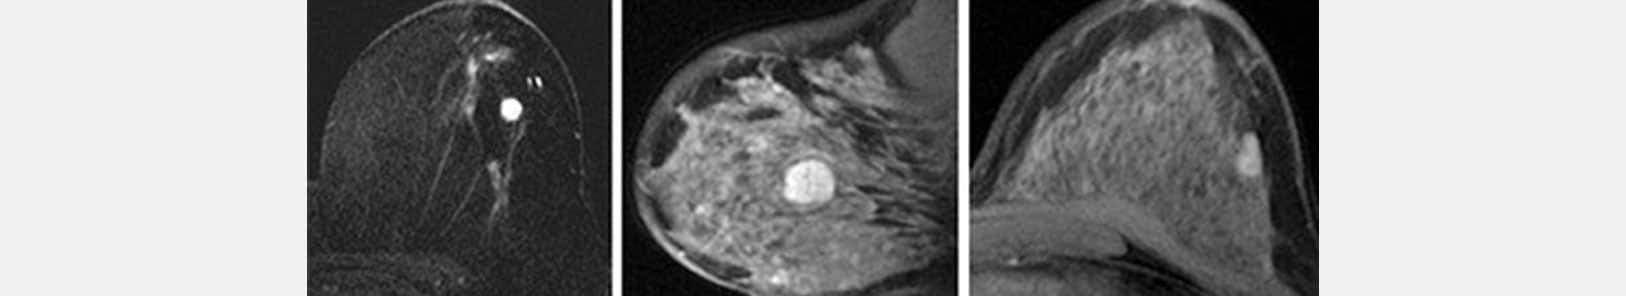

L’IRM est un examen complémentaire.

L’IRM ne remplace ni la mammographie ni l’échographie. Elle ne constitue pas un examen systématique, ni pour le dépistage ni pour le diagnostic de cancer du sein.

C’est un examen complémentaire que le médecin prescrit parfois :

- Dans le cadre du dépistage chez certaines patientes à haut risque de cancer (mutation génétique).

- En cas de suspicion de cancer pour aider au diagnostic lorsque l’imagerie standard ne permet pas de conclure avec certitude.

- En cas de cancer confirmé pour mieux préciser l’étendue des lésions.

- En cours de traitement, en particulier en cas de chimiothérapie pré-opératoire.

Chez une femme non ménopausée, l’IRM devrait idéalement être effectuée entre le 8ème et 12ème jour du cycle.

Chez une femme ménopausée sous traitement hormonal substitutif, il est recommandé d’arrêter ce traitement 6 à 8 semaines avant l’examen.

L’IRM est non irradiante et indolore.

Pourquoi l’IRM mammaire est-elle parfois nécessaire lors du bilan initial ?

L’IRM mammaire offre une cartographie précise des lésions, notamment chez les femmes aux seins denses ou présentant des antécédents génétiques. Elle permet de détecter des lésions non visibles à la mammographie et d’évaluer l’étendue exacte d’une tumeur avant de décider du type d’intervention chirurgicale.